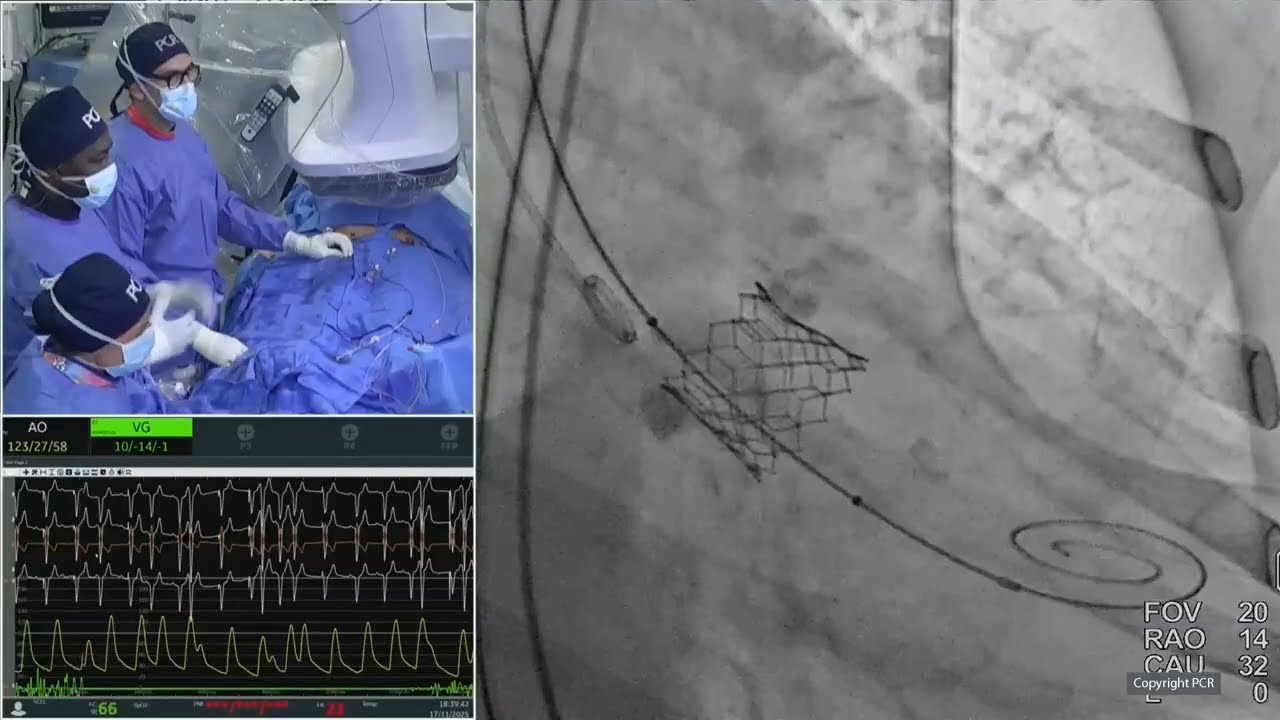

Transcatheter tricuspid valve repair: LIVE Educational Case from University Medical Center - Mainz, Germany